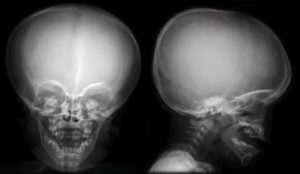

Рентгенограмма черепа выполняется чаще всего в боковой проекции, а также в 2-х дополнительных обзорных проекциях: прямой и аксиальной. Врач, который занимается расшифровкой снимков, должен в совершенстве понимать, что такое рентгеноанатомия черепа, и каковы критерии ее стандартности.

Объективный анализ снимков сможет провести только квалифицированный специалист, поскольку рентгеноанатомия черепа – наиболее сложный объект для рентгенологической диагностики. Врач, делающий расшифровку, должен безошибочно определить, соответствует ли представленная на рентгенограмме картина норме.

В протоколе исследования рентгенолог отмечает соответствие параметров черепа норме (по форме, размерам, толщине), состояние сосудистого рисунка, околоносовых пазух, черепных швов, фиксирует выявленные с помощью анализа отклонения и поражения.